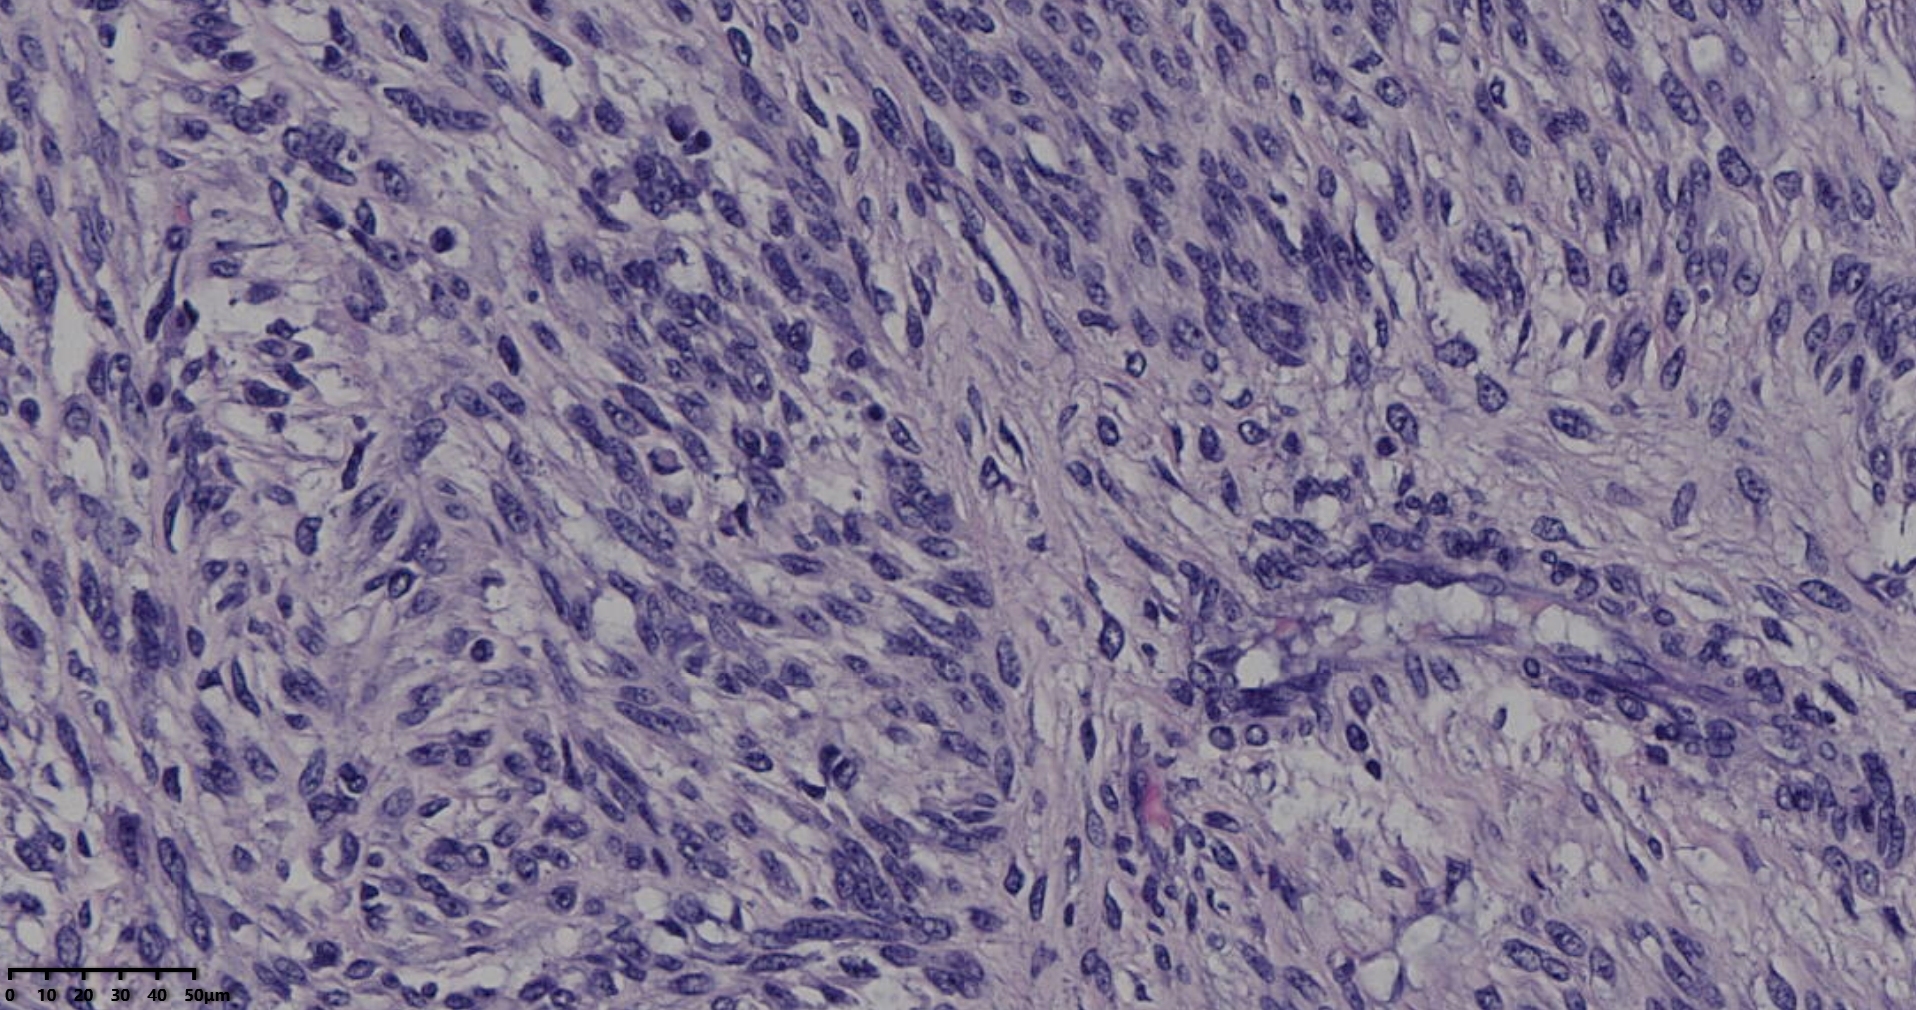

镜下所见小肿物无特殊,大肿物瘤细胞密集,中心区有变性、坏死,瘤细胞核有异型性。大肿物补充取材,发现,部分区域切面灰黄,这个区域,瘤细胞更密集,异型性更显著。肿物边缘有薄层正常平滑肌组织被覆,靠近边缘瘤细胞最密集,局部瘤组织内小血管较丰富。